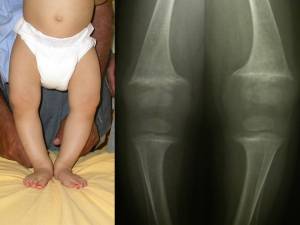

E’ opportuno premettere che un certo grado di varismo-intratorsione tibiale, che potremmo definire fisiologico, è presente alla nascita e persiste fino a 1-2 anni (fig 3).

- Fig. 3: A) Mesi 20, ginocchia vare fisiologiche. B) Stesso paziente all’età di 3 anni con le ginocchia in asse.